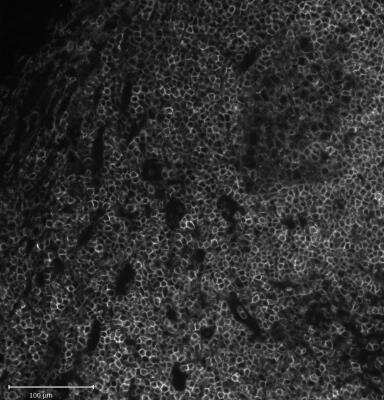

Immunohistochemical Detection of CD45 in Paraffin Embedded Human Tonsil

Formalin-fixed, paraffin-embedded human tonsil (20X) stained with CD45 antibody (2B11 + PD7/26) [NBP2-34287].